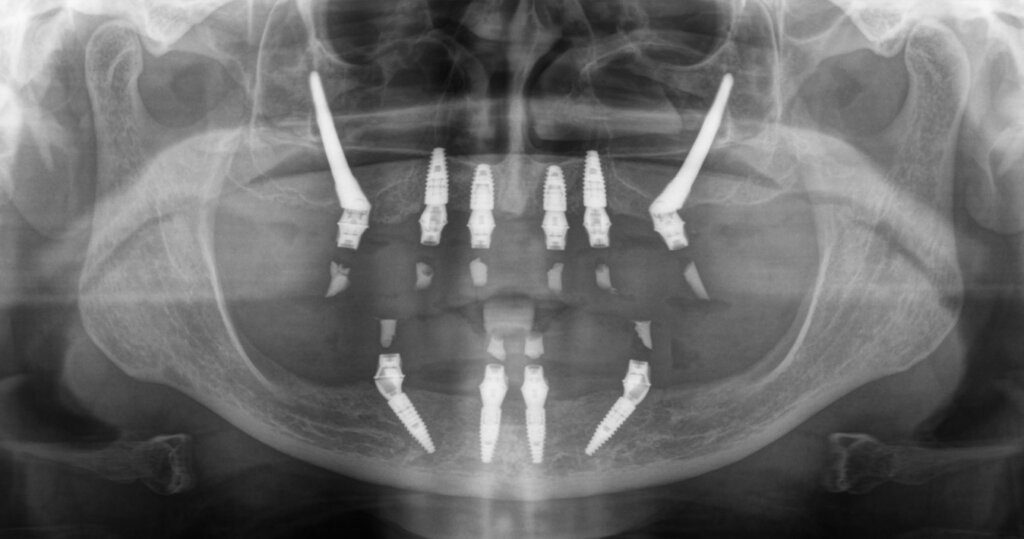

Before Zygomatic Implant Procedure

After Zygomatic Implant Procedure